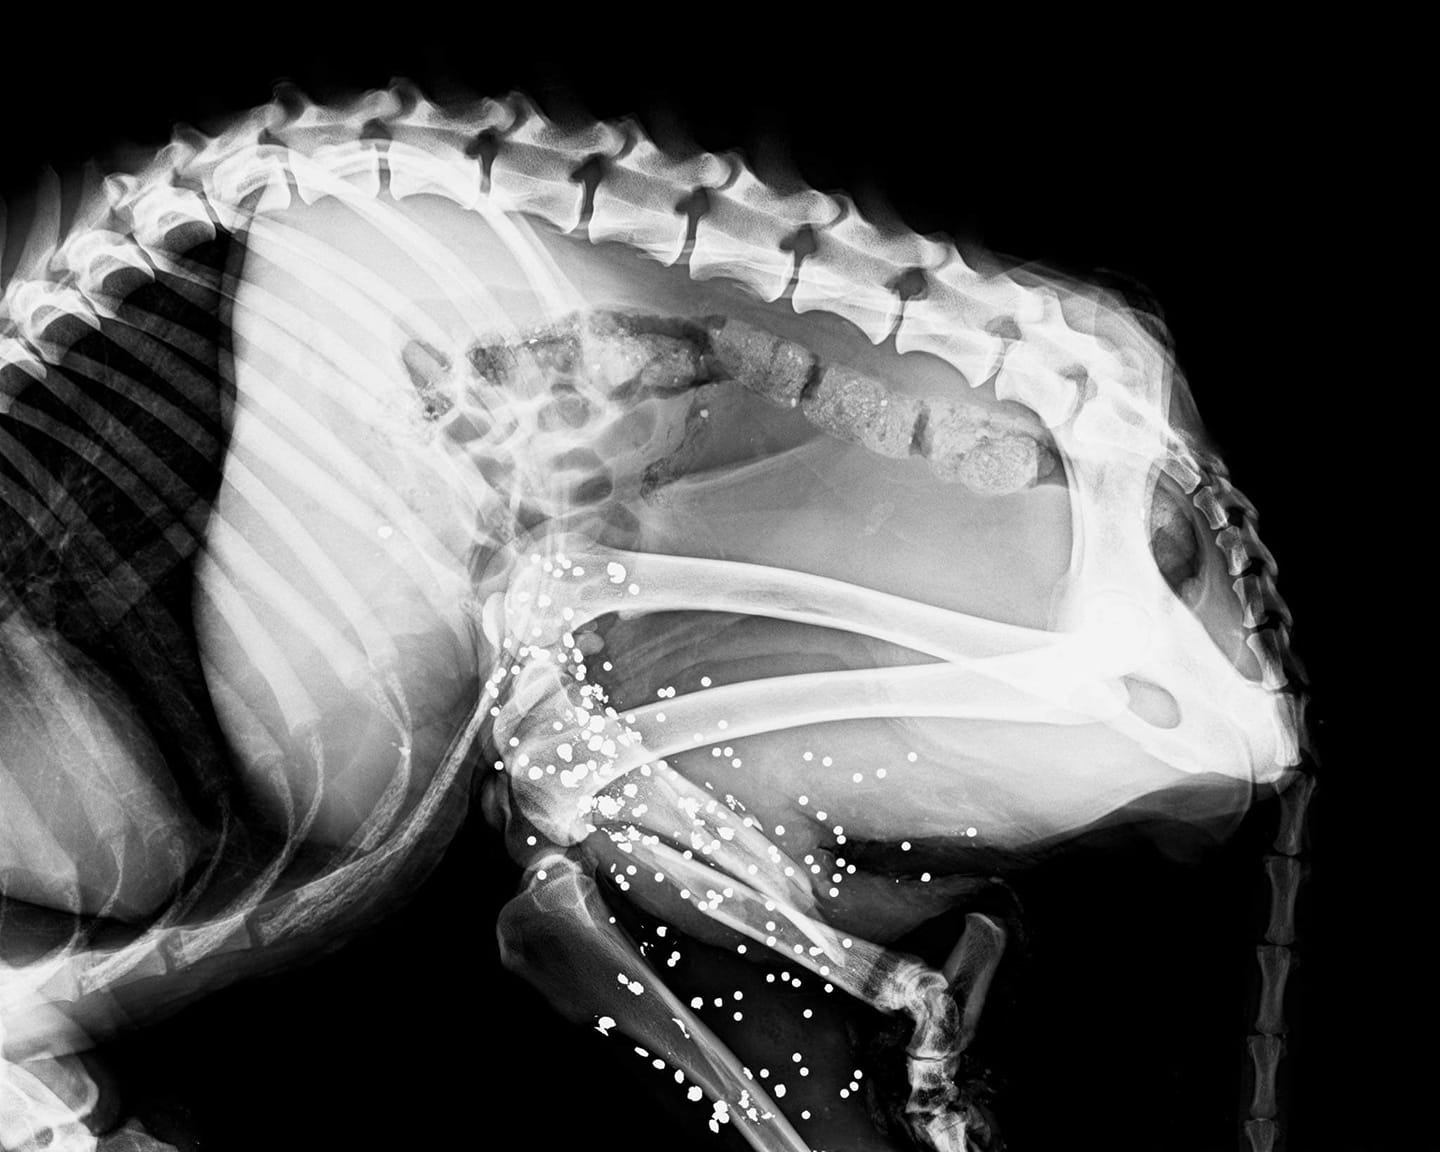

Το σκυλί είναι σε τραγική κατάσταση, τα οστά στα πίσω πόδια του να έχουν βγει από τη σάρκα. Η ακτινογραφία έδειξε ξεκάθαρα ότι η σκυλίτσα είναι πυροβολημένη με κυνηγετικό όπλο, έχει κατάγματα στα πίσω πόδια με νέκρωση και των δύο άκρων και θα γίνει ακρωτηριασμός τους. Στη σπονδυλική στήλη στην περιοχή της λεκάνης υπάρχει μετατόπιση οστών, ουσιαστικά το ζώο έχει μείνει παράλυτο...